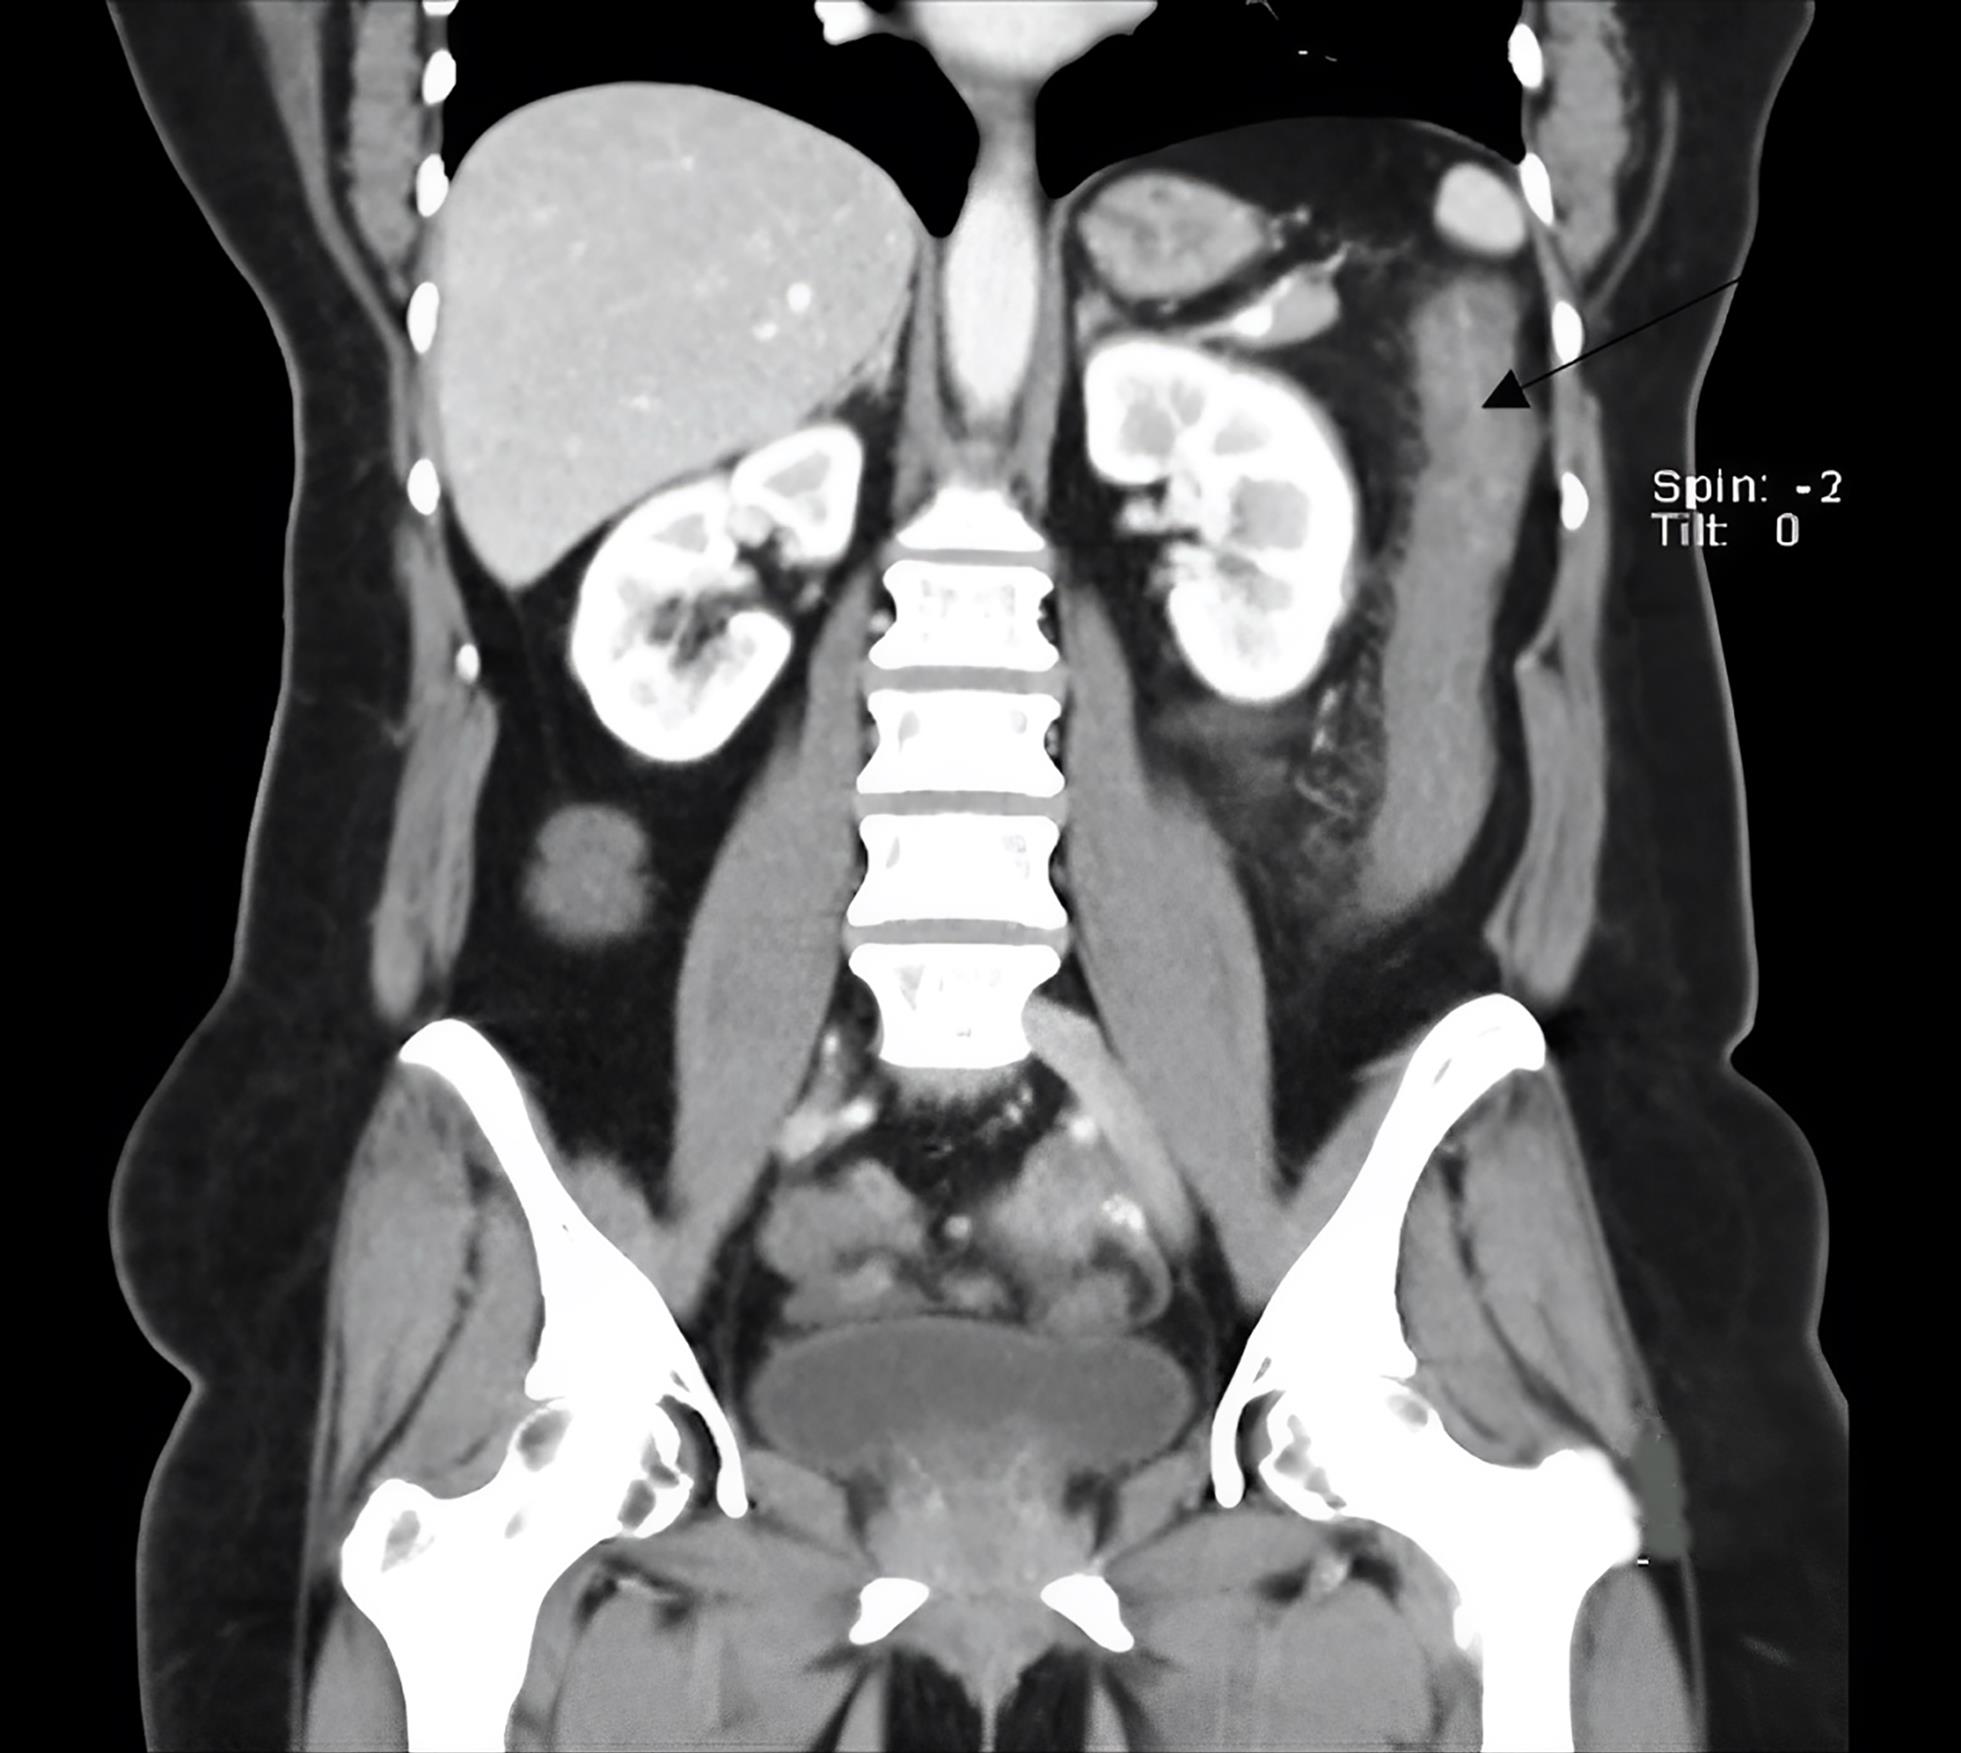

A rectosigmoidoscopy showed ulceration and loss of the normal colonic vascular pattern 30 to 50 cm distal to the anal margin (Fig. 1). Histopathology of the affected area is shown in Figure 2. To rule out conditions beyond the colon, a computed tomography (CT) enterography was performed, which revealed only an inflammatory process in the descending colon (Fig. 3). A colonoscopy confirmed ulceration and inflammation of the colonic mucosa at this site. On the fifth day of hospitalization, the patient experienced another episode of intense abdominal pain and bloody diarrhea one hour after zolmitriptan 2.5 mg was administered for a new migraine episode. After this episode, zolmitriptan was discontinued, and dexamethasone (4 mg intravenous single dose) was initiated. Topiramate was also prescribed, resulting in the complete resolution of the migraine attacks. A neurologic workup for the chronic migraine without aura revealed no organic cause.

Computed tomography enterography on coronal section, revealing inflammation in the descending colon (white arrow).

Fig. 3  Computed tomography enterography on coronal section, revealing inflammation in the descending colon (white arrow).